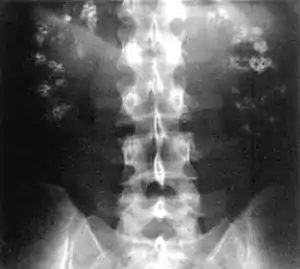

Nephrocalcinosis, once known as Albright's calcinosis after Fuller Albright, is a term originally used to describe deposition of calcium salts in the renal parenchyma due to hyperparathyroidism. The term nephrocalcinosis is used to describe the deposition of both calcium oxalate and calcium phosphate.[1] It may cause acute kidney injury. It is now more commonly used to describe diffuse, fine, renal parenchymal calcification in radiology.[2] It is caused by multiple different conditions and is determined progressive kidney dysfunction. These outlines eventually come together to form a dense mass.[3] During its early stages, nephrocalcinosis is visible on x-ray, and appears as a fine granular mottling over the renal outlines. It is most commonly seen as an incidental finding with medullary sponge kidney on an abdominal x-ray. It may be severe enough to cause (as well as be caused by) renal tubular acidosis or even end stage kidney disease, due to disruption of the kidney tissue by the deposited calcium.

| Bilateral nephrocalcinosis seen on an abdominal x-ray | |